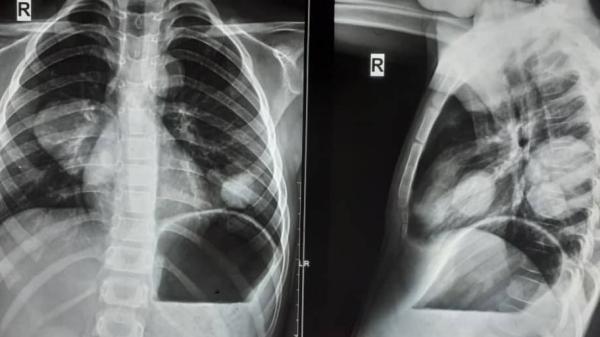

Болезнь развивается медленно и может поражать печень, легкие и другие органы, образуя кисты, которые часто требуют хирургического вмешательства. Симптомы эхинококкоза зависят от локализации кист и могут включать боли в животе, кашель, одышку, слабость и аллергию.